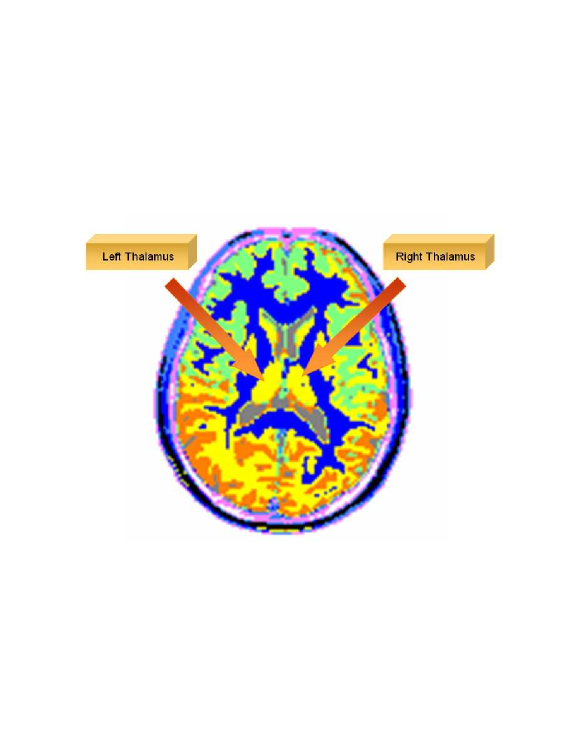

This thesis is composed of three parts. In the first part, we introduce the novel Diffusion Bases methodology (theory, algorithms and applications) for dimensionality reduction. Specifically, in Chapter 2 we give an in depth introduction to dimensionality reduction where we provide a formal definition of the problem followed by a description of the current state-of-the-art techniques for dimensionality reduction. In Chapter 3 we describe in details the diffusion maps technique [45] since it is closely connected to our diffusion Bases (DB) dimensionality reduction scheme which we introduce in Chapter 4. The DB algorithm explores the variability among the coordinates of the original data while the DM explores local neighborhoods of points in the dataset. Both algorithms use a random walk model. The DB algorithm uses the eigenvectors of the corresponding Markov matrix as an orthonormal system and projects the original data onto it to obtain the low-dimensional representation. The DM algorithm, on the other hand, builds a different Markov matrix whose eigenvectors constitute the low-dimensional representation. In Chapter 5 we provide an introduction to hyper-spectral imagery which includes the terminology, concept, motivation and common applications in this area. Chapter 5 is necessary for the understanding of Chapters 6 and 9. Chapters 6-8 include successful applications of the DB scheme. Specifically, in Chapter 6, the DB dimensionality reduction scheme is used for segmentation of hyper-spectral images and for the detection of anomalies in images of this type. In Chapter 7, the DB scheme is incorporated in an algorithm for segmentation of multi-contrast MRI images. Segmentation of video sequences which uses the DB scheme is described in Chapter 8.

In this thesis, a novel coherent integrated methodology is introduced (theory, algorithm and applications) to reduce the dimensionality of high-dimensional datasets. The method constructs a diffusion process among the data coordinates via a random walk. The dimensionality reduction is obtained based on the eigen-decomposition of the Markov matrix that is associated with the random walk. The proposed method is utilized for: (a) segmentation and detection of anomalies in hyper-spectral images; (b) segmentation of multi-contrast MRI images; and (c) segmentation of video sequences.